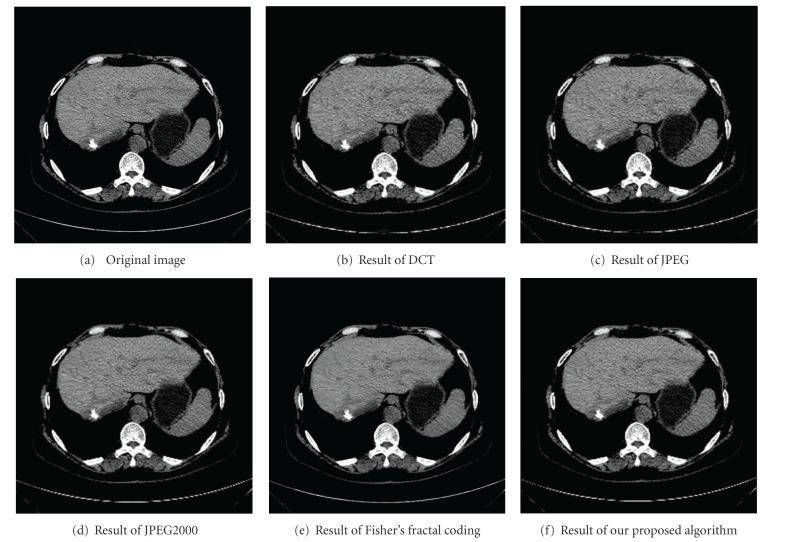

An optimized medical image compression algorithm based on wavelet transform and improved vector quantization is introduced. The goal of the proposed method is to maintain the diagnostic-related information of the medical image at a high compression ratio. Wavelet transformation was first applied to the image. For the lowest-frequency subband of wavelet coefficients, a lossless compression method was exploited; for each of the high-frequency subbands, an optimized vector quantization with variable block size was implemented. In the novel vector quantization method, local fractal dimension (LFD) was used to analyze the local complexity of each wavelet coefficients, subband. Then an optimal quadtree method was employed to partition each wavelet coefficients, subband into several sizes of subblocks. After that, a modified K-means approach which is based on energy function was used in the codebook training phase. At last, vector quantization coding was implemented in different types of sub-blocks. In order to verify the effectiveness of the proposed algorithm, JPEG, JPEG2000, and fractal coding approach were chosen as contrast algorithms. Experimental results show that the proposed method can improve the compression performance and can achieve a balance between the compression ratio and the image visual quality.